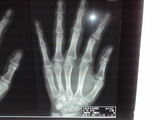

くるんと回り、手を見ると人差し指が普段とは違う方向を向いていた(笑)

小池に「あれ?小池、俺の指曲がってない??」と聞くとにやけながら「はい!親指に近くなってます」・・・

信号待ちでこりゃ~画像でも撮っておくかとパシャっと撮るも左手が震えていてうまく取れなかった。

血がドクドクと出るわ、指が感覚無いわだったが、何故か指があった安堵感で全然冷静で、自分で曲がった指をちょっと戻そうと頑張ったが無理だった。(グラップラー刃牙の花山薫なら余裕だろ)

自治医大に行き、もう一度レントゲン。

脱臼しているところをグリグリ入れられ、結局「都賀病院に手の名医がいるから1/4に精密検査して下さい」だって。しかも「靱帯が切れてる可能性があるから手術かも?」っとあやふやな事を言われた。